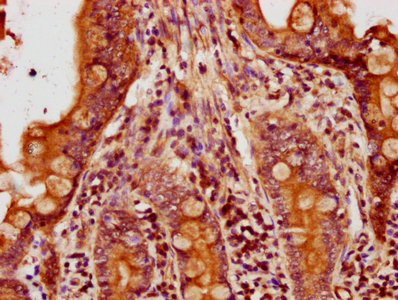

Immunohistochemistry of paraffin-embedded human endometrial cancer using CSB-PA01629A0Rb at dilution of 1:100